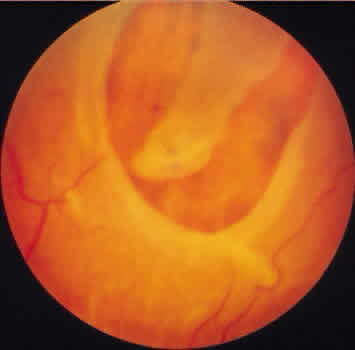

DEGENERATIVE RETINOSCHISIS

Degenerative retinoschisis, a more extensive trophic process, presents as a round or ovoid area of retinal splitting with a smooth fusiform elevation of the inner layer (Fig. 17). The schisis is surrounded on all sides by typical cystoid degeneration; the retinal pillars of the cystoid degeneration as well as the broken pillars near the margin of the schists are prominent. Vessels are located in the inner retinal layer, the intraretinal cavity is optically empty, and the outer retinal layer is moderately irregular in contour.13,14

Fig. 17. Typical degenerative retinoschisis.Note extensive region of typical cystoid degeneration with a rounded and elevated posterior margin. In the center (arrow), radial columns are randomly disrupted, causing a disturbance in coarse surface pattern. (× 18.)

On clinical examination, typical degenerative retinoschisis appears as round or ovoid areas of retinal splitting with fusiform elevation of the inner layer (Fig. 19). The stippled pattern of surrounding typical cystoid degeneration extends on the inner layer for a variable distance; centrally the inner layer, which contains the blood vessels, is thin and smooth. On contact lens ophthalmoscopy, the inner layer is finely textured, some of the retinal vessels are attenuated, and there is a variable number of tiny, glistening, white dot opacities on the vitreous side. The outer layer, found external to the optically empty cavity, is best seen with indirect ophthalmoscopy when it becomes white on scleral depression. It is somewhat uneven, giving an appearance of finely hammered or beaten metal. Typical degenerative retinoschisis does not extend posteriorly to threaten the macula, and it is not often associated with breaks in either retinal layer; it rarely requires treatment.

Fig. 19. Clinical appearance of typical degenerative retinoschisis: diagram of involved area and ocular fundus photographs showing optic disc, macula, and posterior portion of schisis. Within the schisis and adjacent to the margin is coarse stippling related to broken retinal pillars.